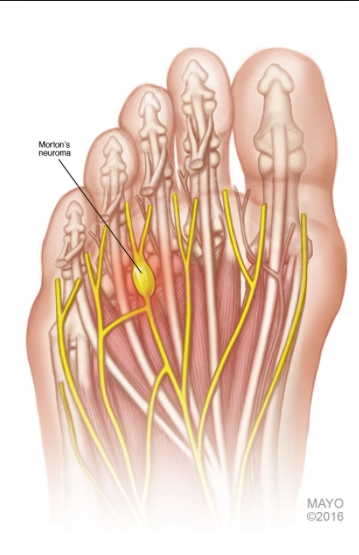

Morton Neuroma

This patient's presentation suggests an interdigital (Morton) neuroma, which commonly occurs in runners. The disorder is not a true neuroma but is a mechanically induced neuropathic degeneration of the interdigital nerves that causes numbness, aching, and burning in the distal forefoot from the metatarsal heads to the third and fourth toes. The symptoms are worsened by walking on hard surfaces and wearing tight or high-heeled shoes.

The diagnosis of Morton neuroma is primarily made clinically. On examination, squeezing the metatarsal joints will cause pain on the plantar surface of the foot along with crepitus between the third and fourth toes (Mulder sign). Treatment involves metatarsal support with a bar or padded shoe inserts to decrease pressure on the metatarsal heads. Surgery is usually reserved for patients who fail conservative treatment.